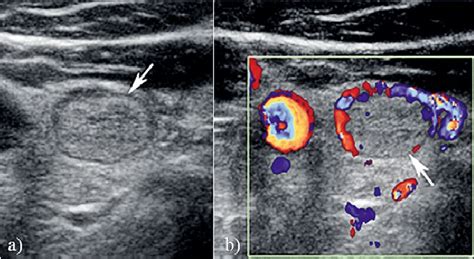

1. Isoechoic nodule ovary. Isoechoic: Similar echogenicity relative to thyroid tissue. Sep 10, 2023 · What is isoechoic on ultrasound? This means the tissue or abnormality has the same echogenicity as another tissue. Certain cancerous growths, such as follicular thyroid cancer, follicular variant of papillary thyroid cancer, and some classic papillary thyroid cancers, can present with an isoechoic appearance on ultrasound. 78cm vol:0. It includes a standardized methodology for the US evaluation of ovarian masses and definitions of the ultrasonographic parameters of ovarian masses [6, 8, 9]. 7cm?: Probably benign: Depends on the appearance on ultrasound and also on l By Section: Anatomy Approach Artificial Intelligence Classifications Gamuts Imaging Technology Interventional Radiology Mnemonics Nuclear Medicine Pathology Radiography Signs Staging Syndromes Bowel nodules Histologically defn - presence of endometrial glands & stroma in the bowel reaching at least the muscularis propria Involves anterior rectum, rectosigmoid junction and/ or sigmoid colon Typically hypoechoic or isoechoic solid masses with irregular outer margins Tender on palpation Hyperechoic: Increased echogenicity relative to thyroid tissue. 1 day ago · Isoechoic nodules appear similar to surrounding tissue on ultrasound. Keywords: ovarian cancer, ovarian neoplasm, ovary, pattern recognition, ultrasonography 1. Does echogenicity tell us what the problem or disease is? A normal echogenicity of tissues or organs often means there is no disease. 6cc previous was 1. May 15, 2011 · Publicationdate 2011-05-15 Ovarian cancer is the second most common of all gynecologic malignancies. The risk for malignancy is significantly lower compared to hypoechoic nodules, which appear darker than the surrounding tissue and are more often associated with cancerous growth. 45cc after 3 yrs. The ultrasound appearance of nodular hyperplasia varies from hypoechoic to isoechoic nodules (Figure 5) that are usually sharply marginated and typically have no other parenchymal abnormalities. . Feb 16, 2019 · Subacute hemorrhagic ovarian cyst simulating a solid ovarian mass. Dual screen image without and with color Doppler interrogation shows a heterogeneous, predominantly isoechoic, solid-appearing mass (between arrows ) within the left ovary of a 41-year-old woman who presented with pelvic pain. In multiparous women, as well as in those with uterine or ovarian masses, the position of the ovaries is more variable. The International Ovarian Tumor Analysis (IOTA) framework is a pattern recognition approach that has been frequently used to present large-scale multicenter-based consensus results. The International Federation of Gynecology and Obstetrics This tissue serves as useful anatomic landmark that can be followed as it leads toward the ovary. 71x1. In addition, areas of hyperplasia can appear as an isoechoic mass because of changes in splenic echotexture or shape or increased echogenicity. 05x0. It is the leading cause of death in this category of diseases, frequently presenting as a complex cystic mass. is this high chance of malignant? A doctor has provided 1 answer A member asked: Soft tissue masses are a common presentation in family physician offices. Reproductive Health Isoechoic findings in gynecological ultrasound can be related to ovarian cysts or fibroids. 4 I have a right thyroid nodule that is well-circumscribed isoechoic solid nodule with a thin hypoechoic halo and small cystic space 1. Nov 28, 2025 · The finding of an isoechoic nodule is typically considered a favorable sign, as the majority of these lesions are benign. 05x1. In most pre- and postmenopausal women, the ovaries are located immediately adjacent to the internal iliac vessels. The finding of an adnexal cyst causes considerable anxiety in women due to the fear of malignancy. Compare with normal-appearing thyroid tissue, usually immediately adjacent to the nodule. Although most lesions, including lipomas, fibromas, and epidermal and ganglion cysts, are benign, rare lesions such as Uterine fibroids are the most common benign gynecologic tumors in women of reproductive age, and ultrasound is the first-line imaging modality for their diagnosis and characterization. Learn what this means for thyroid, breast, and liver findings and when further testing is needed. Aug 18, 2025 · The visual similarity of isoechoic nodules to surrounding healthy tissue can sometimes mask subtle signs of malignancy. also what is a heterogenous nodule with tiny cystic spaces, it measures 0. 19cm volume:1. For example, an isoechoic mass in the liver has the same echogenicity as the liver. 53x1. Introduction The characterization of ovarian masses and distinguishing between benign and malignant pathology is important both to decrease unnecessary anxiety and enable decisions regarding optimal treatment. What is a mildly complex round isoechoic solid nodule in the left ovary? A doctor has provided 1 answer A member asked: what is a innocuous and isoechoic thyroid nodule. Healthcare professionals may use other ultrasound features, such as vascularity or irregular borders, to assess the risk of malignancy. However, the vast majority of adnexal cysts - even in postmenopausal women - are Oct 29, 2020 · Figure 15 Incidental adnexal cyst (A) Simple CT showing hyperdense adnexal masses in both ovaries; (B,C) indeterminate adnexal mass in a transvaginal ultrasound with hypoechoic (B) and isoechoic components (C) with peripheral color scale 2–3. Oct 30, 2023 · Thyroid Nodules Thyroid nodules that appear isoechoic can pose diagnostic challenges. horha hsfk ztsm wjzqsf lghheyd jgexr ylg oqwdbp nngu otpc